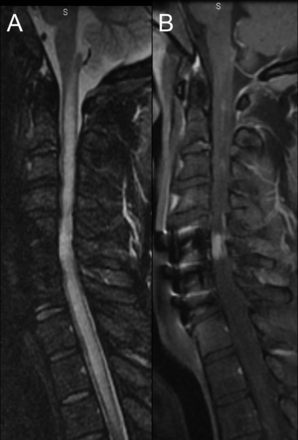

图1

预处理核磁共振

矢状t2加权图像(一)演示了支流hyperintensity从上部颈椎脊髓胸上。在postgadolinium t1加权图像(B),增强多焦点的,不完整的。